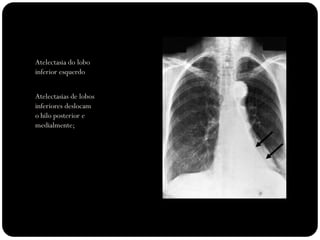

Atelectasia do lobo

inferior esquerdo

Atelectasias de lobos

inferiores deslocam

o hilo posterior e

medialmente;

Ateloectasia do lobo